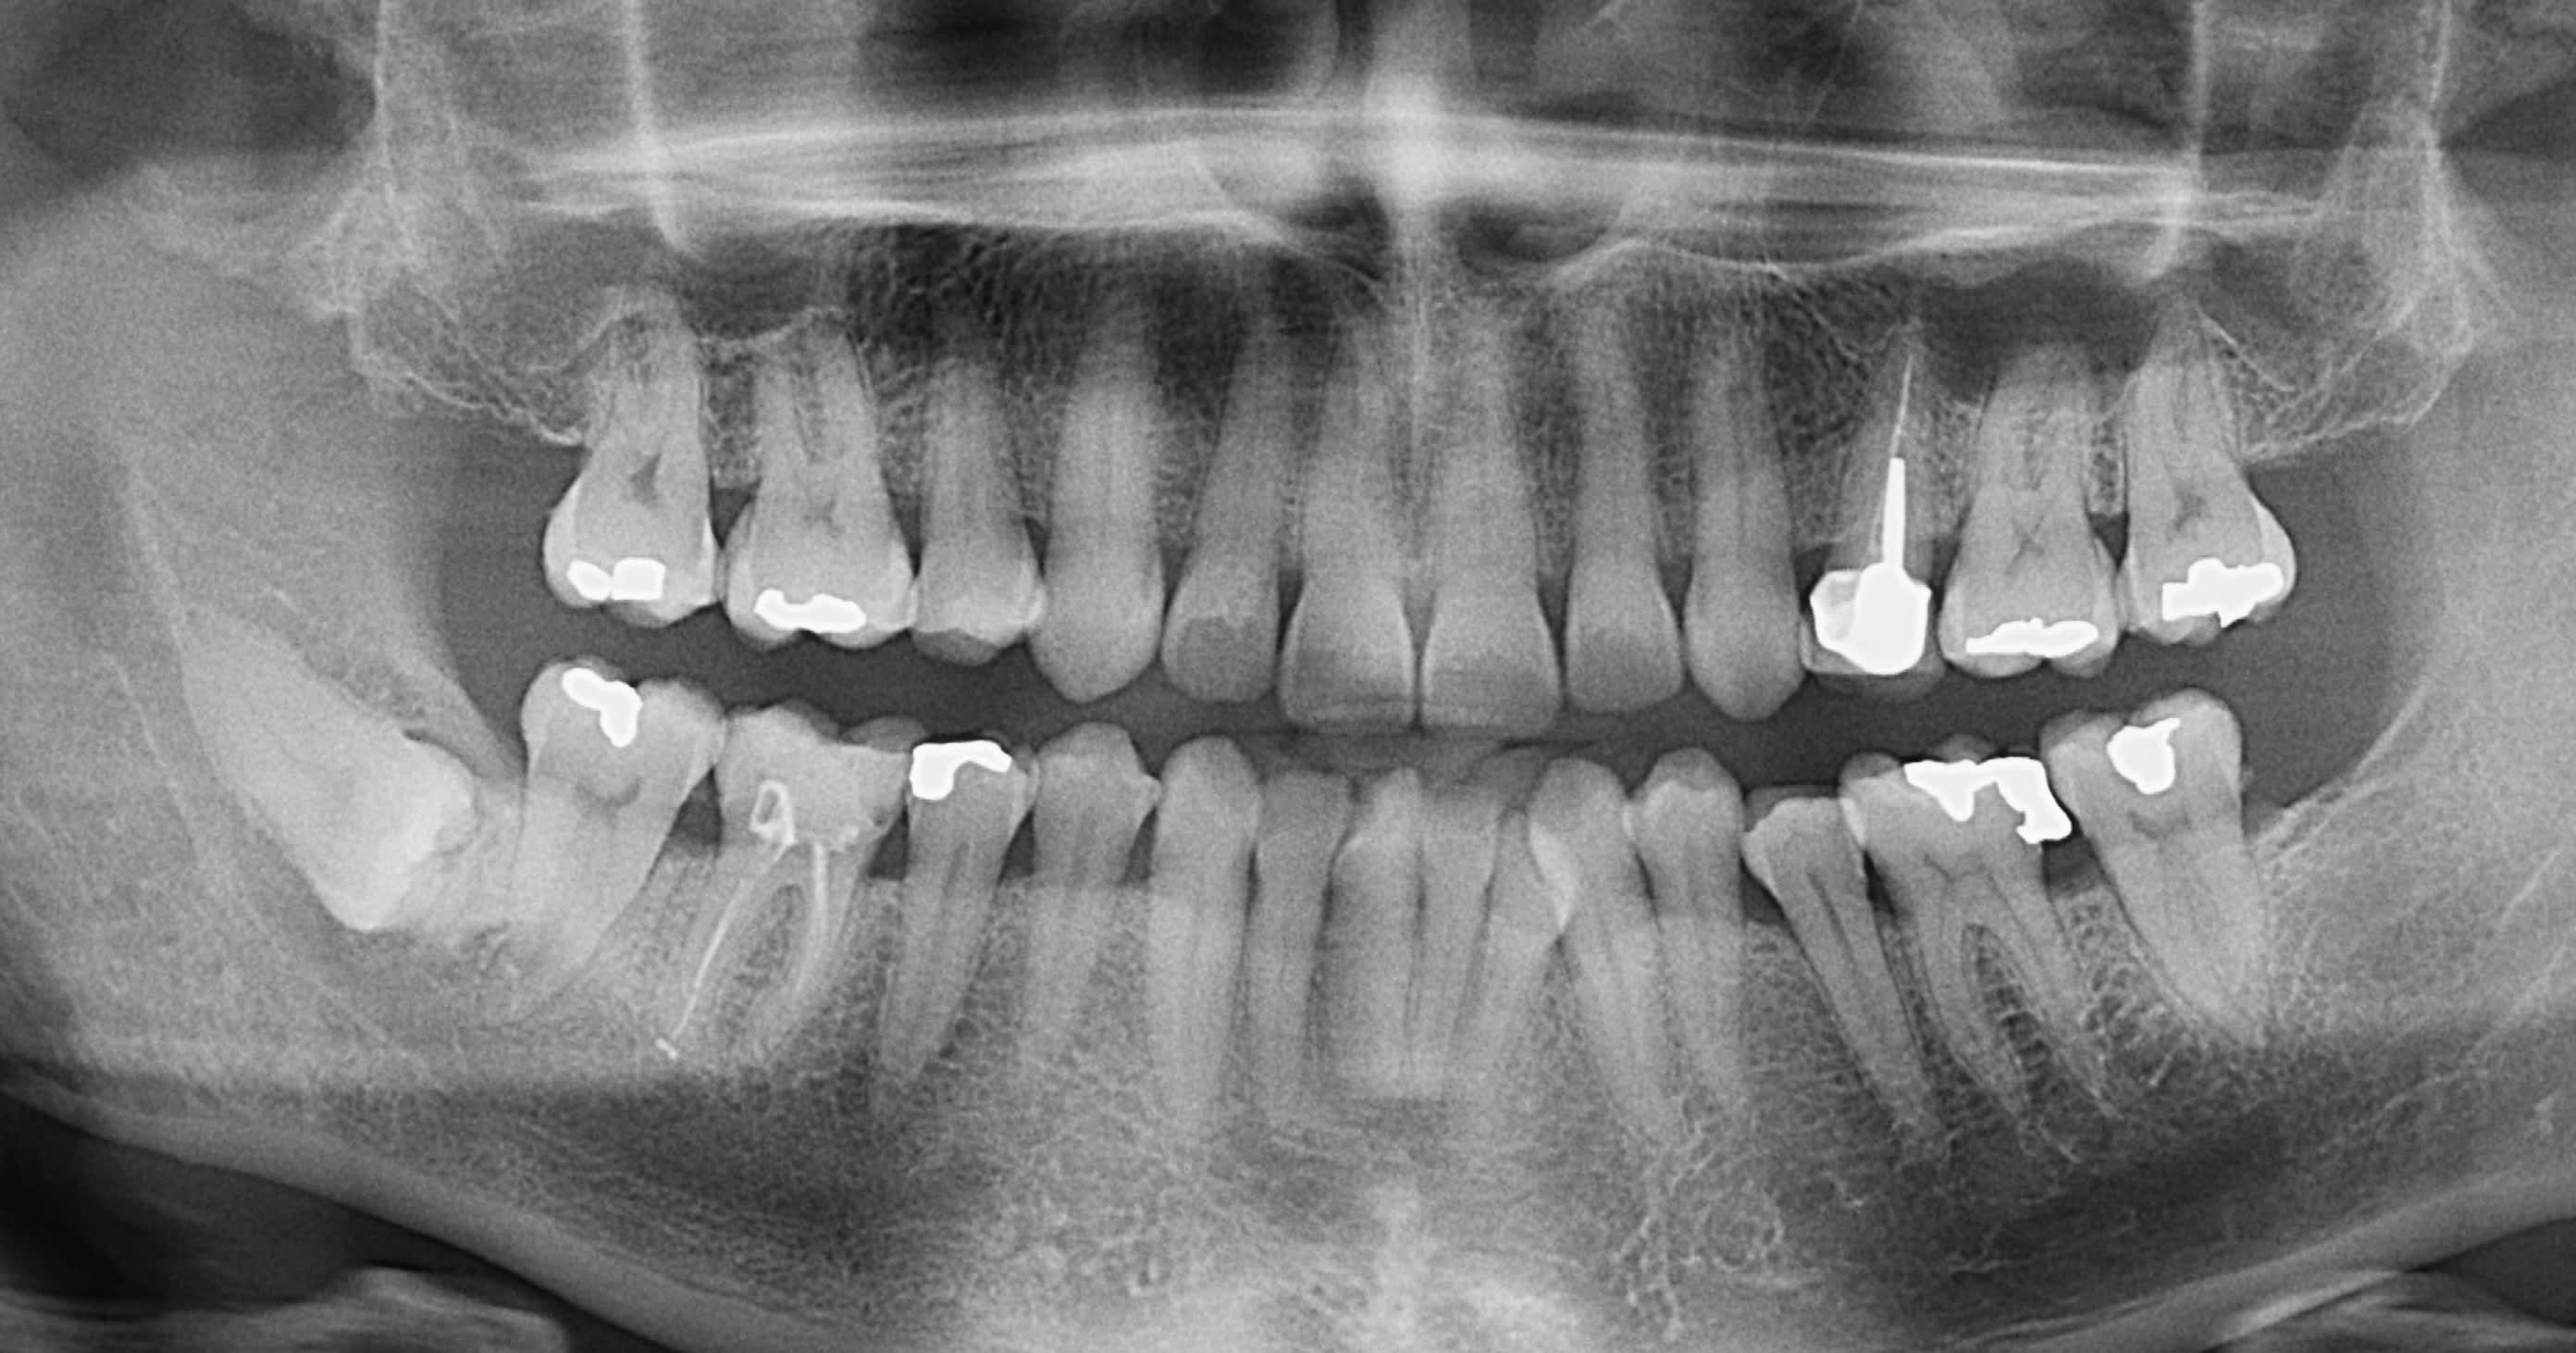

10-07-2025 Panoramique Fin.JPG